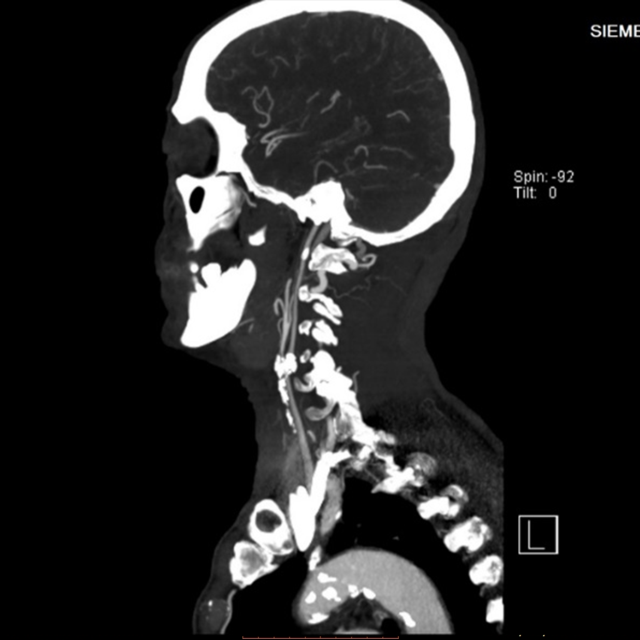

▲術(shù)前CTA檢查見患者主動脈弓、頸動脈多處粥樣硬化斑塊,左頸總動脈分叉處血管重度狹窄